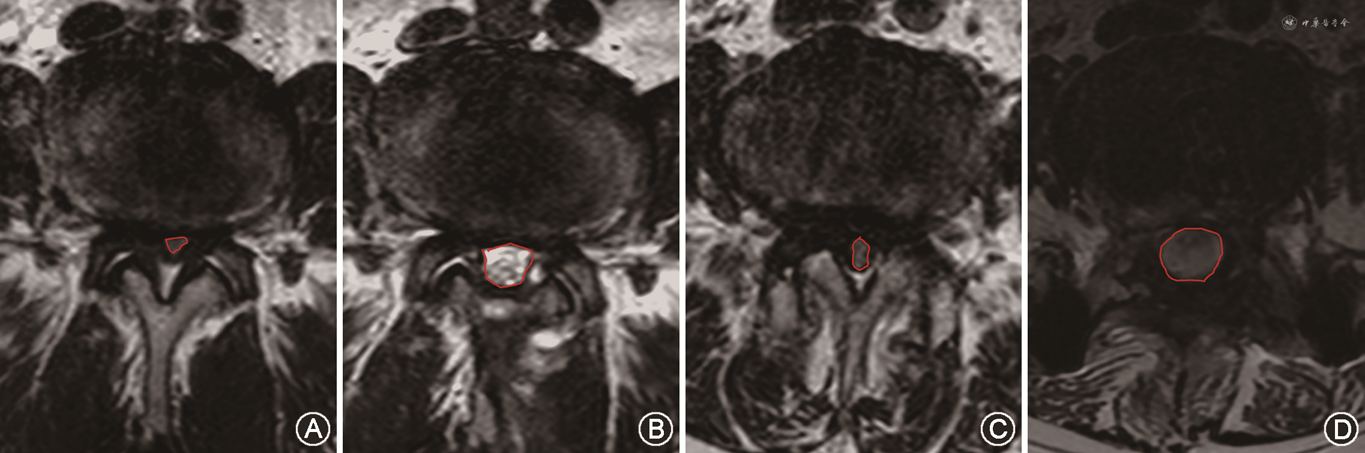

所有患者均在术前和术后6个月内完善腰椎MRI检查,并由两名独立的影像医生在病变节段的椎间盘水平,间隔3 mm连续取3个横断面T2加权像,通过影像系统描绘硬膜囊的边界计算DSCA,并观察硬膜囊的形态,通过Schizas标准分级评估椎管狭窄的程度(图3)。所有数据均由3名临床医生独立记录,并取平均值进行最终统计分析。

两组术前DSCA差异无统计学意义(P>0.05),两组术后的DSCA均较术前显著扩大(P<0.05),且PLIF组术后的DSCA较UBE组更大(P<0.05);在Schizas标准分级中,UBE组术前C级17例,D级13例,术后恢复至A级25例,B级5例;PLIF组术前C级18例,D级16例,术后恢复至A级30例,B级4例,两组术后的Schizas标准分级均较术前显著改善(P<0.05),而两组术后对比差异无统计学意义(P>0.05)(表4)。

两组腰椎管狭窄症患者的影像学结果情况

| 组别 | 例数 | DSCA(mm2,) | Schizas标准分级(A/B/C/D)(例) | ||

|---|---|---|---|---|---|

| 术前 | 术后 | 术前 | 术后 | ||

| UBE组 | 30 | 45.1±11.8 | 129.2±15.7a | 0/0/17/13 | 25/5/0/0 |

| PLIF组 | 34 | 50.0±10.3 | 152.5±12.7a | 0/0/18/16 | 30/4/0/0 |

| t值 | -1.75 | -6.55 | - | - | |

| P值 | 0.850 | 0.025 | 0.770b | 0.570b | |

注:DSCA为硬膜囊横截面积;UBE为单侧双通道内镜;PLIF为后路腰椎椎体间融合术;与术前相比,aP<0.05;bFisher精确检验